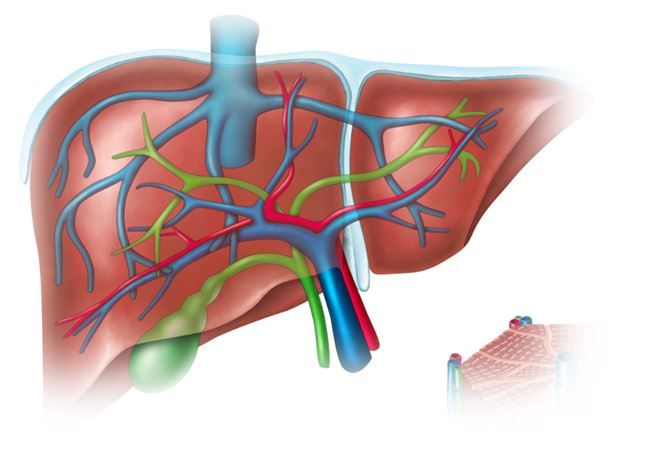

Two scenarios: a 42-y/o man with MRCP findings of concern and a 35-y/o woman s/p RNY and C-sections, with RUQ pain. Your solutions?

RUQ pain x3 days, fevers x24h. LFTs are elevated. Which of these tests should you order?